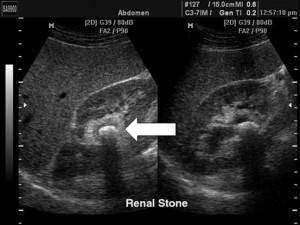

Камни в почках на УЗИ, фото. Виден плотный гиперэхогенный кальцинат в почечной лоханке с акусической тенью.